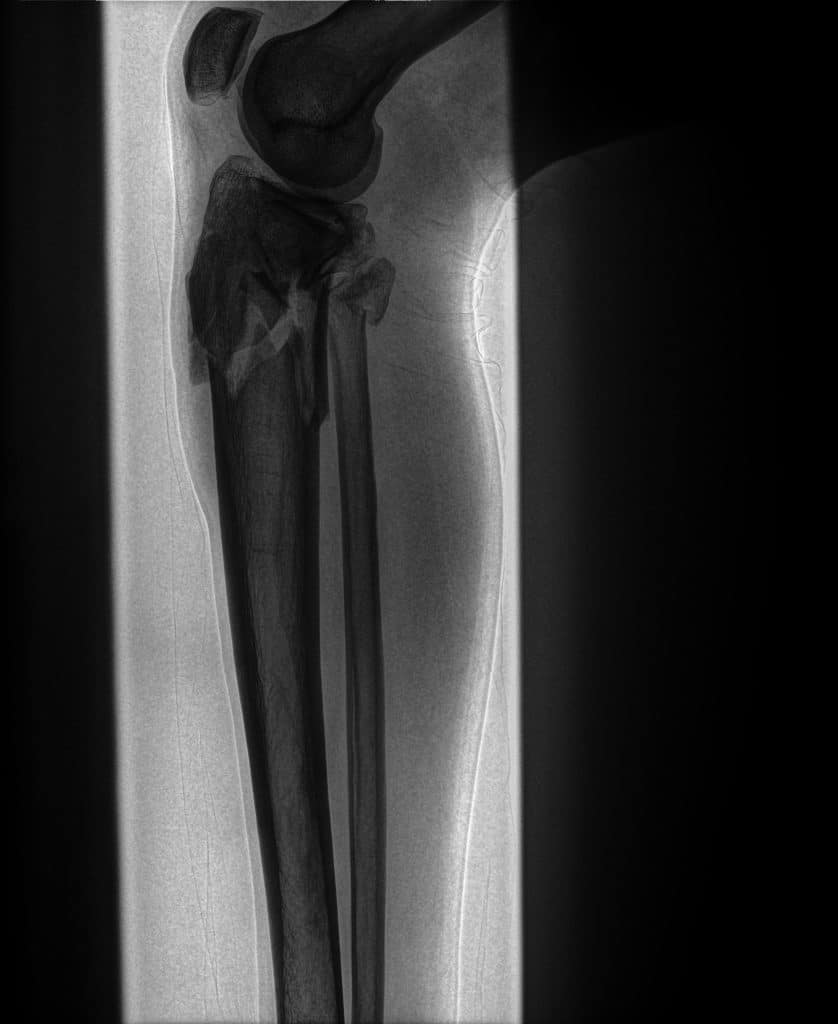

Bone images generated by spectral imaging emphasize calcified structures, allowing clinicians to review skeletal anatomy with reduced soft-tissue overlap.

The Bone image is more adept at presenting the bony skeleton in a manner that delineates it better than a conventional DR image. By displaying only on the areas of highest subject density, the SpectralDR™ technology yields improved visualization of both healthy and diseased bone.

SpectralDR bone images emphasize skeletal structures, allowing clearer visualization of the fracture compared with the conventional radiograph.